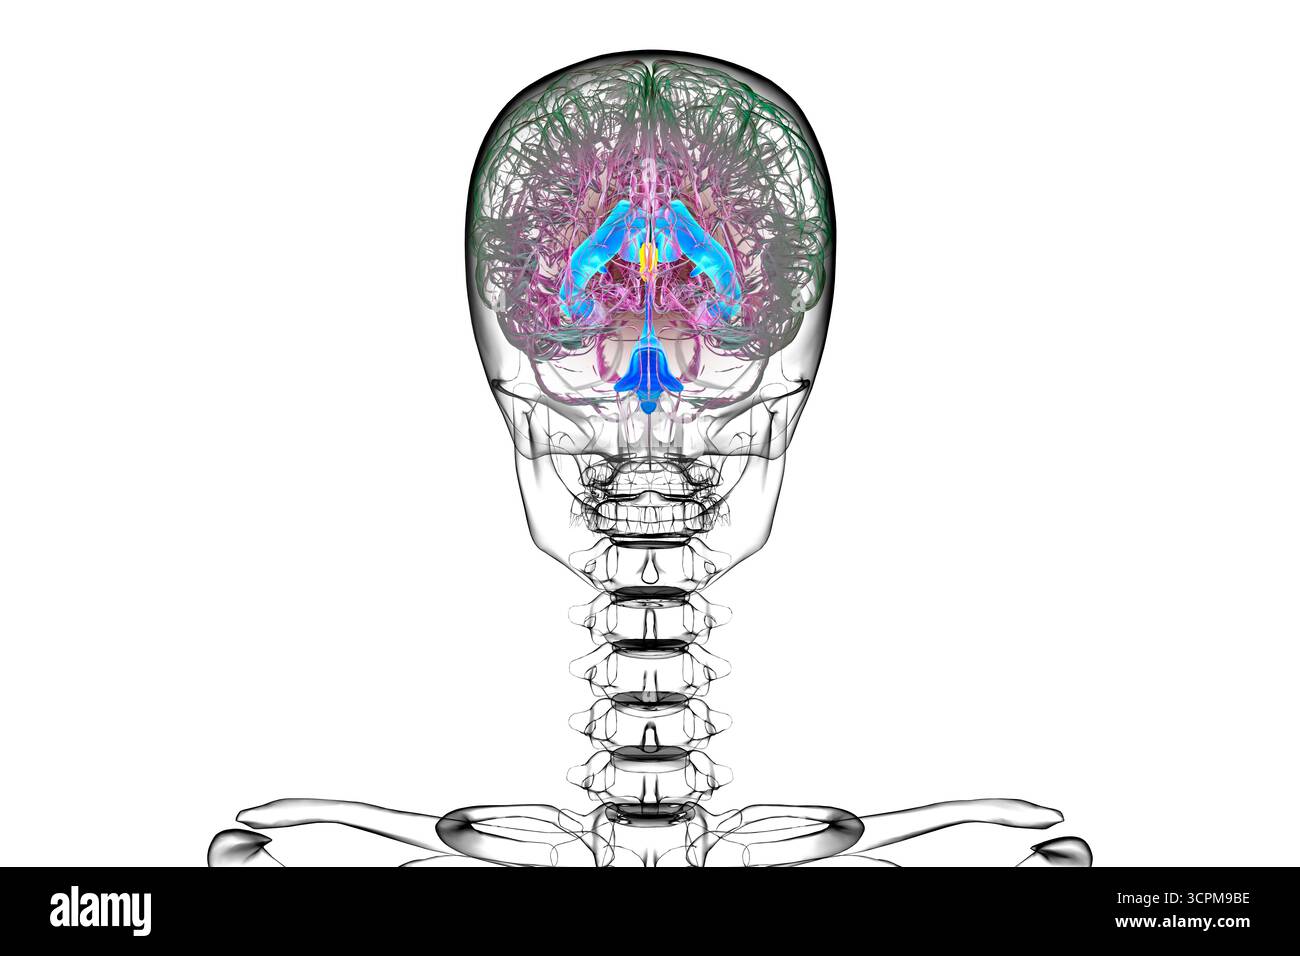

RF3CN8WHP–Illustration des vergrößerten lateralen und dritten Ventrikels des Gehirns (Hydrozephalus), hervorgerufen durch einen Hirntumor, der den Aquädukt des Gehirns komprimiert.

RF3CPM9C1–Illustration des dritten Hirnventrikels, einer lebenswichtigen Komponente des Hirnventrikulärsystems.

RF3CPM9BH–Illustration des dritten Hirnventrikels, einer lebenswichtigen Komponente des Hirnventrikulärsystems.

RF3CPM9BF–Illustration des dritten Hirnventrikels, einer lebenswichtigen Komponente des Hirnventrikulärsystems.

RF3CPM9BE–Illustration des dritten Hirnventrikels, einer lebenswichtigen Komponente des Hirnventrikulärsystems.

RF3CPM9BX–Illustration des dritten Hirnventrikels, einer lebenswichtigen Komponente des Hirnventrikulärsystems.